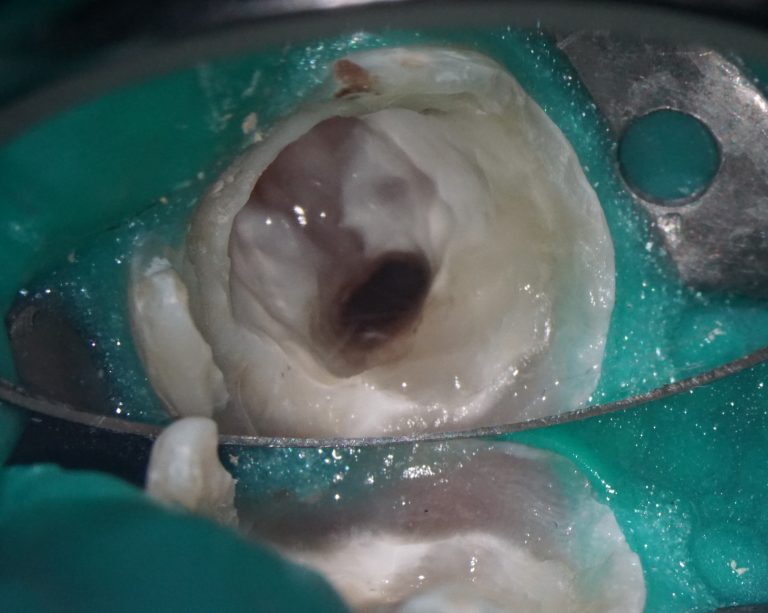

The result of collaboration with Diagnocat AI is a favorable outcome of the orthodontic and surgical stages of treatment